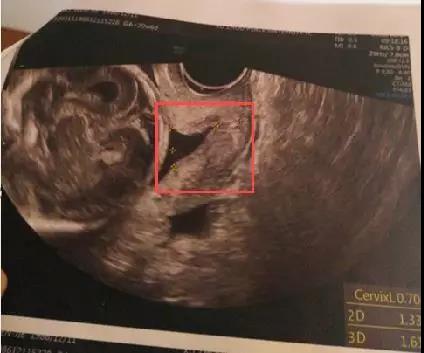

▲孕21周时彩超显示小洁的宫颈长度较短

10月17日,正值超声专家邱伟修博士受邀来我院会诊的日子,对这位大神早有耳闻的小洁也早早预约了他的会诊名额,就在邱博士为她做常规四维彩超检查时,却发现小洁:宫颈机能不全,随时可能出现胎膜早破、先兆流产等严重风险。